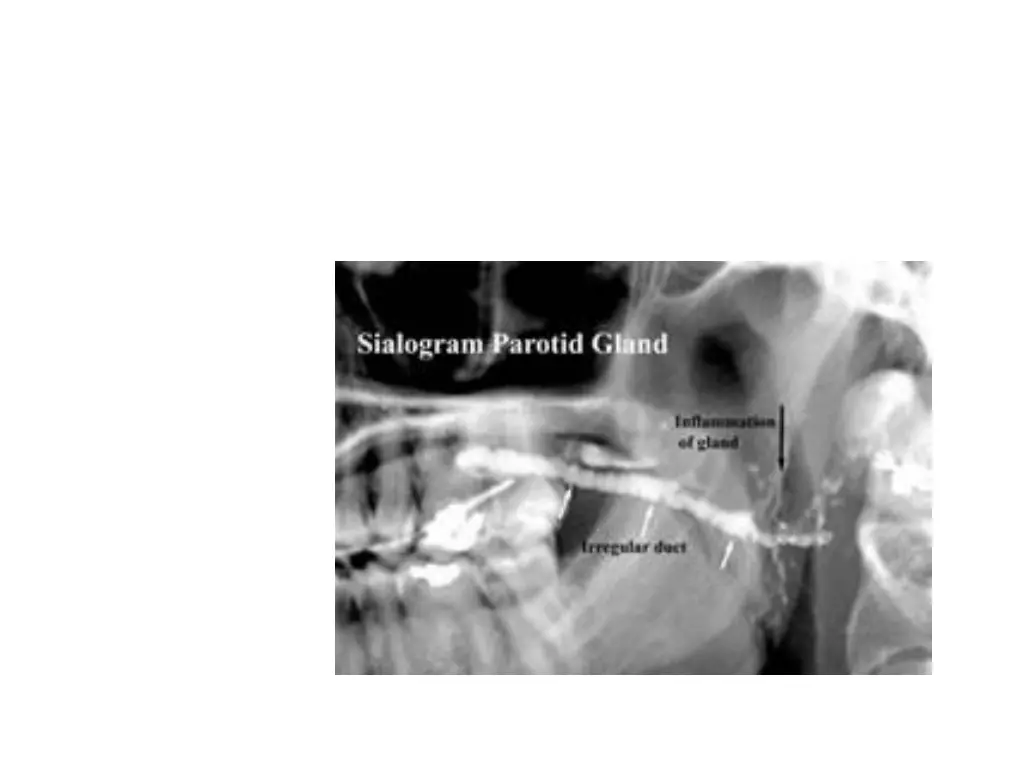

Conventional sialography Is a r/g technique wherein a r opaque contrast agent is infused into the ductal system of salivary gland before imaging with plain films It is the most detailed way to image the ductal system Survey or scout film is usually made before the infusion of contrast solution into ductal system A lacrimal or periodontal probe is used to dilate the sphincter at ductal orifice before the passage of cannula connected by extension tubing to a syringe containing contrast agent

Lipid soluble and non lipid soluble contrast solution is then slowly infused until the pt feels discomfort Filling phase is monitored by fluoroscopy or with static films Intent is to opacify the ductal system all the way to acini Image of ductal system appears tree limbs Image of acinar filling appears as tree comes to bloom Gland is allowed to empty for 5 mts without stimulation If postevacuation images shows contrast agent, a sialogogue such as lemon juice or 2% citric acid may be admininstered to augment evacuation by stimulating secretion

Bacterial sialadenitis Is contraindicated in acute infections coz of disrupted ductal ept where extravasation of contrast agent may occur and have foreign body reaction and severe pain Ept flattening may lead to midly terminated terminal ducts and sac like acini Sac like acinar areas are referred to as sialectasia An even distribution throughout the gland is seen in recurrent parotitis and AI disordersabscess cavities appear on CT as walled off areas of lower attenuation within an enlarged gland

Sialodochitis Syn: ductal sialadenitis It is inflammation of the ductal system of salivary glands It is seen in submandibular and parotid glands It is seen as dialtation of ductal system on sialography If interstitial fibrosis develops, it appears as sausage string of main duct and its major branches produced by alternate strictures and dilations